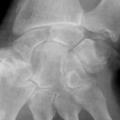

Chondrocalcinose articulaire

ARTHROPATHIES A CRISTAUX

Image